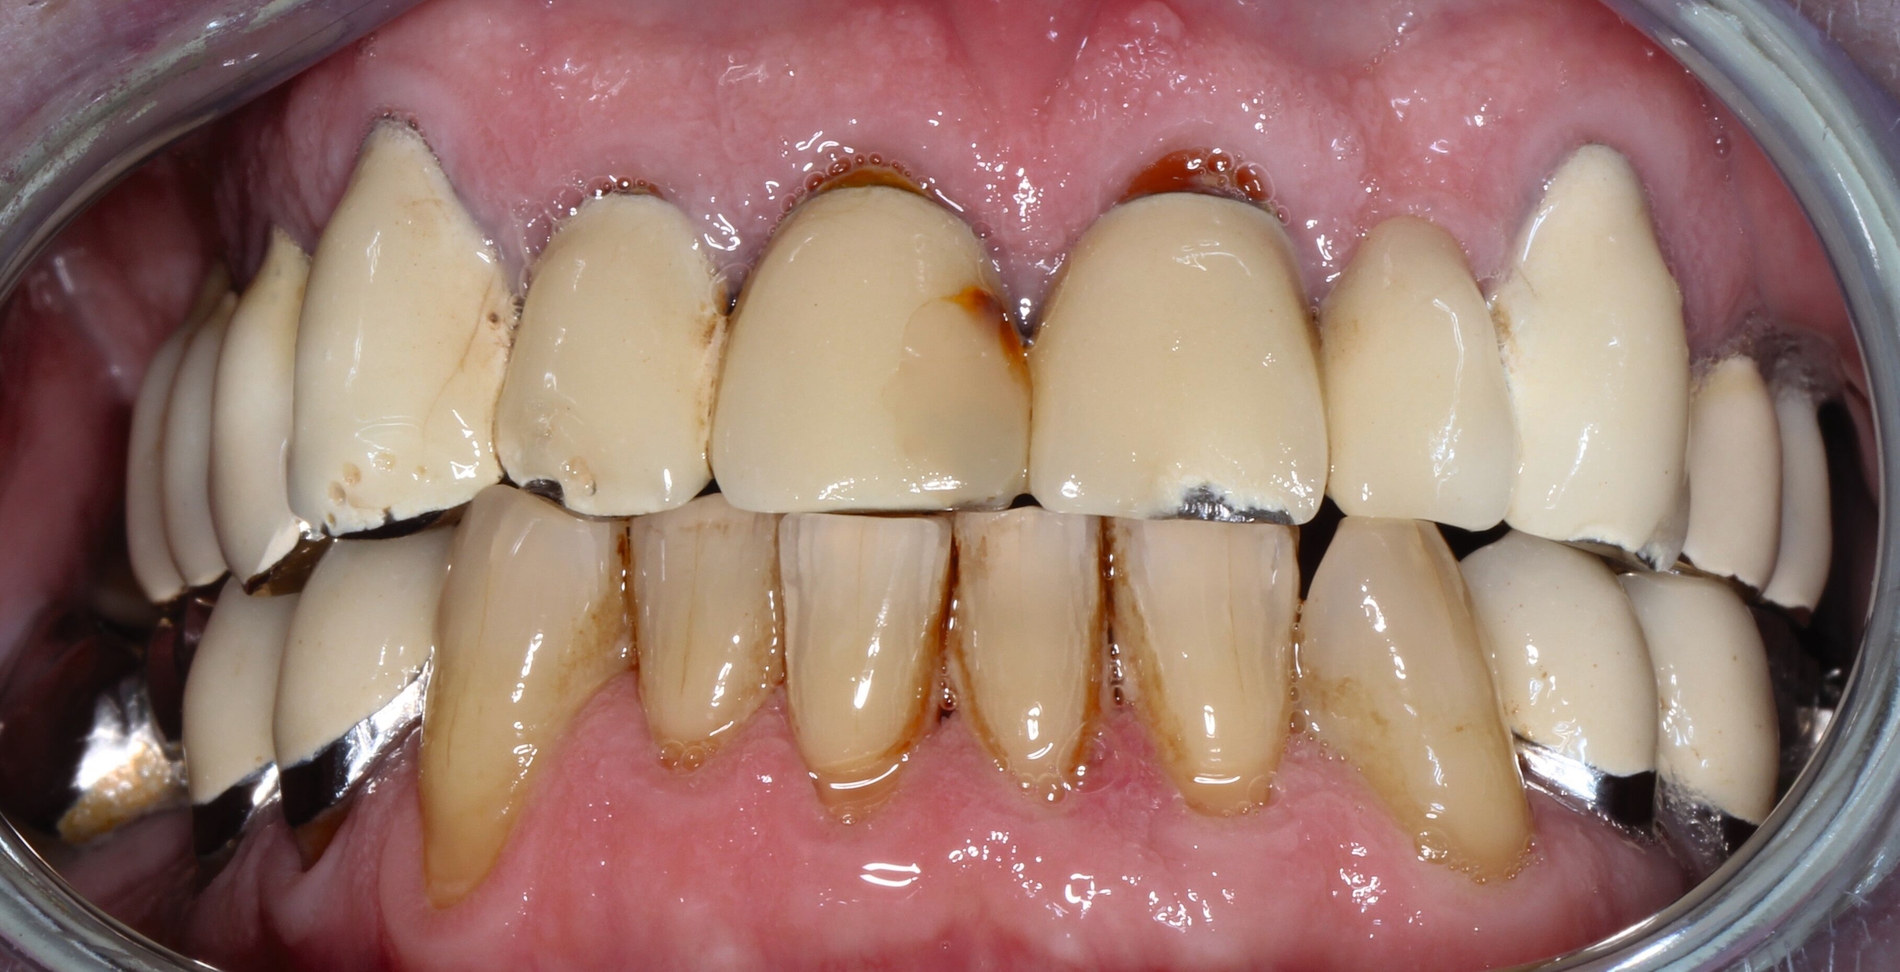

Der Patient stand unter der Dauermedikation von Metformin 500 mg, Ramipril 5 mg, Torasemid 10 mg, Metohexal 47,5 mg, Simvastatin 20 mg, Tamsulosin 0,4 mg und 3 mg Marcumar (INR 2,5–2,8) bei Zustand nach einer Bypass-Operation im Jahr 2019. Klinisch zeigten sich im Oberkiefer insuffiziente, verblockte und verblendete NEM-Kronen mit beidseitigen Gold-Extensionen distal, die über Geschiebe mit dem anterioren Anteil verschraubt waren (Abbildungen 1 und 2). Der Patient berichtete, dass die vorhandenen Kronen und Brücken 1984 eingesetzt worden seien.

Besonders auffällig war eine Dezementierung, die klinisch durch rechtsseitigen Druck und Zug mit einer Pinzette und daraufhin austretende Sulkusflüssigkeit in Regio 14 detektiert wurde. Da entsprechend des synoptischen Behandlungskonzepts [Naumann et al., 2010] bei prothetischer Neuversorgung eine gesamte Evaluation der Restpfeiler erfolgen muss, wurden zunächst die Kronen im Oberkiefer durch Schlitzen und Aufbiegen entfernt. Erst danach ließ sich deren Erhaltungswürdigkeit abschließend beurteilen.

So war der Zahn 14 tief kariös zerstört und nicht-erhaltungswürdig, was mit dem Bild der wahrscheinlich seit Längerem bestehenden Dezementierung korrelierte (Abbildung 3). Die Brücken im Unterkiefer wurden als suffizient befundet. Die Ruheschwebelage wurde mithilfe des Zielinsky-Zirkels auf 2 mm bestimmt. Parodontologisch zeigten sich stabile Verhältnisse. Ein Parodontaler Screening-Index (PSI) wurde erhoben (3-1-1-1-2-2). Der hier auffällige Zahn 14 wurde bereits zuvor beim klinischen Befund als nicht-erhaltungswürdig eingestuft und im Verlauf extrahiert.